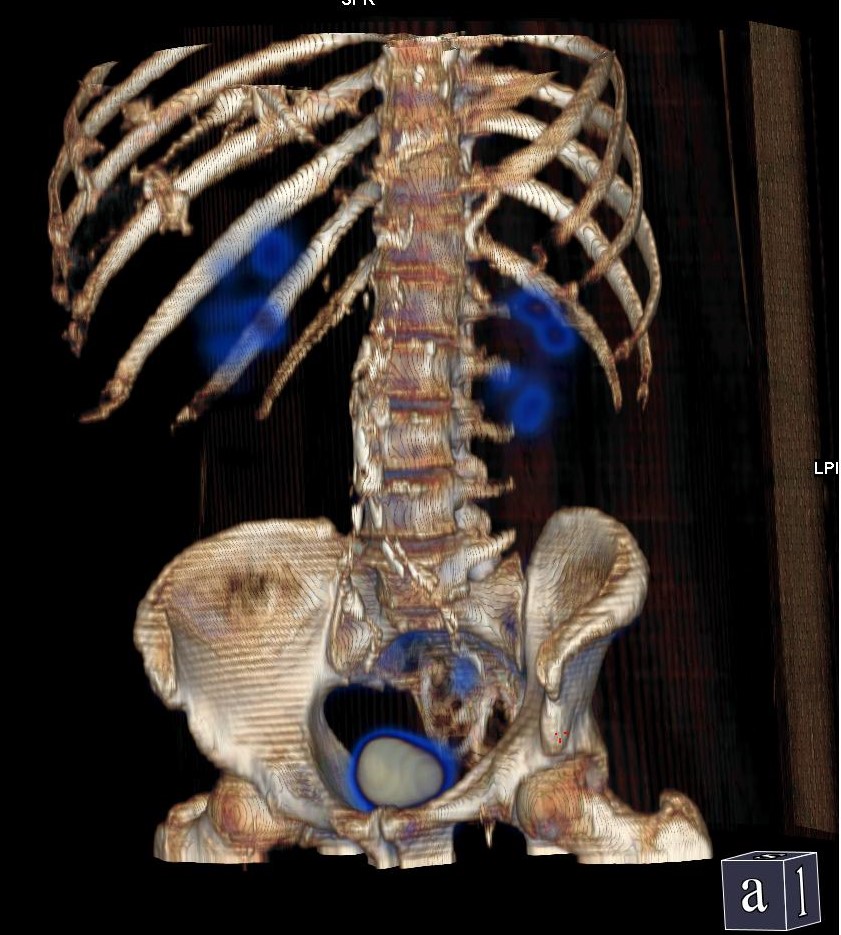

Il Servizio di Medicina Nucleare di Humanitas Istituto Clinico Catanese ha compiuto un grande salto in avanti nell’imaging diagnostico grazie all’acquisizione di una nuova gamma camera di ultima generazione, un tomografo ibrido che unisce le funzionalità di una gamma camera e di una TC: la SPECT/TC. La gamma camera è dotata di caratteristiche peculiari (detettori Slim Elite NXT compatti, wide gantry, robotica ultra-fast) che permettono di ottenere le massime performance nell’esecuzione delle indagini scintigrafiche sia in termine di “qualità” delle immagini diagnostiche che in termine di “riduzione” della dose di radiofarmaci necessari.

“La robotica ultra-fast del tomografo – dichiara il dott. Demetrio Aricò, responsabile del Servizio – consente di configurare il tomografo ibrido non solo in base alla tipologia dell’esame, ma anche in base alle necessità cliniche del paziente: acquisizioni in piedi, su barella o seduti. È la macchina che si adatta al paziente e non il contrario. L’altro grande vantaggio ottenuto con il nuovo tomografo è la SPECT/TC, nuova tecnica di acquisizione delle immagini che garantisce un significativo incremento dell’accuratezza diagnostica delle indagini scintigrafiche.“

Esattamente come avviene per l’imaging PET, il paziente potrà eseguire al termine della scintigrafia – che dura circa 3-15 minuti – una scansione TC senza scendere dal tomografo permettendo al Medico Nucleare di giungere alla conclusione diagnostica in modo veloce ed accurato. Il percorso diagnostico, in questo modo, diventa estremamente più breve in quanto non ci sarà più bisogno di eseguire un ulteriore approfondimento radiologico dopo la scintigrafia, già compreso nella scintigrafia stessa! Il paziente, grazie all’utilizzo del nuovo tomografo, non non dovrà più eseguire due esami distinti e separati in giorni differenti.

“Le immagini sono paragonabili a quelle delle PET – prosegue Aricò – ma con alcune differenze in quanto la SPECT/TC è eseguita solo in caso di necessità (come approfondimento richiesto dal Medico Nucleare) e solo sul distretto interessato come il torace, l’addome, il cervello, ecc., ottimizzando le tempistiche e il comfort del paziente. La SPECT/TC è molto utile in diverse applicazioni cliniche e coinvolge trasversalmente molte discipline mediche come la cardiologia, l’ortopedia, l’endocrinochirurgia, le malattie infettive ed anche la neurologia.“